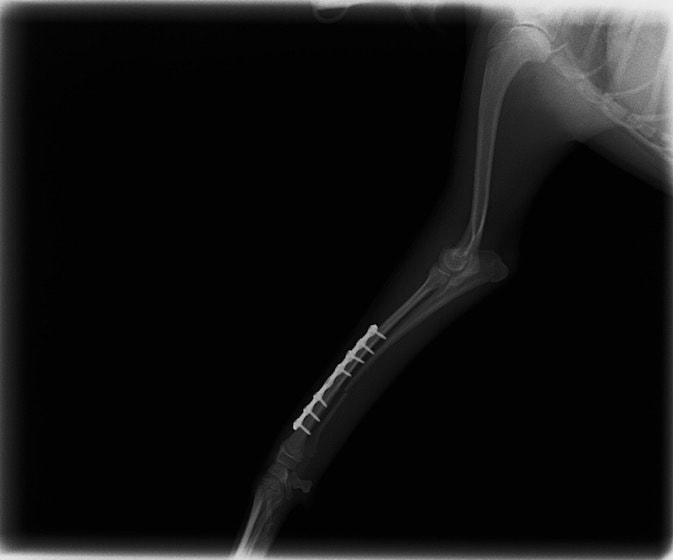

橈尺骨骨折 : 症例1 | 症例2 | 症例3 | 症例4 | 症例5 | 症例6 | 症例7

当院ではAdvanced Locking plate system(ALPS)と、Locking compression plate system(LCPS)という骨接合法で骨折症例の治療を行っています。

Advanced Locking Plate System

従来型のプレートのように広い面積で骨と接するプレートを用いて固定を行った場合、プレート下の骨はプレートとの接触面において血行が絶たれ壊死し、それがリモデリングされると骨密度が低下する。この骨密度の低下防ぐために、骨折部局所への血行を温存することの重要性が近年改めて認識されるようになってきている。Advaed Locking Plate System (ALPS)は従来型のプレートシステムの欠点を改良し、より使いやすく、より骨への血行を阻害しないようにというコンセプトで作られた。